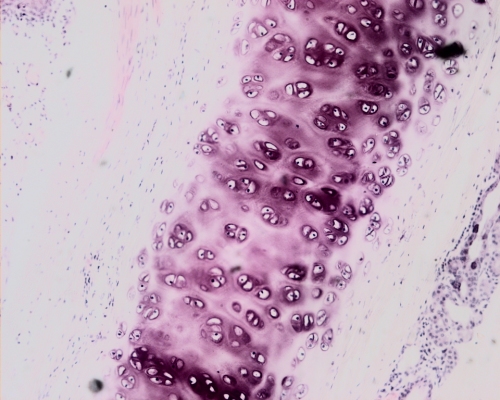

Hyaline cartilage